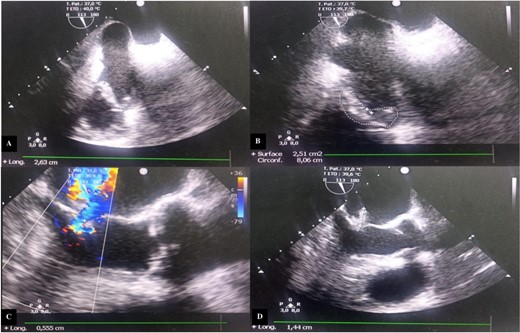

Transthoracic echocardiography (TTE) revealed a mitral valve with moderate, eccentric, double-jet regurgitation, perforation of the anterior mitral leaflet, and the presence of vegetation on the atrial side of the anterior mitral leaflet, which was pedicled, mobile, and measuring 15 × 7.6 mm. The tricuspid valve had vegetation interfering with valve closure, measuring 21 × 12 mm, causing significant central tricuspid regurgitation, with a systolic pulmonary artery pressure (SPAP) at 64 mmHg (Fig. 1).

Transthoracic echocardiography images. (A) Vegetation attached to the atrial side of the anterior mitral leaflet measuring 15 × 7.6 mm. (B) Significant mitral regurgitation. (C) Vegetation attached to the free edge of the anterior tricuspid leaflet measuring 21 × 12 mm. (D) Massive tricuspid regurgitation.